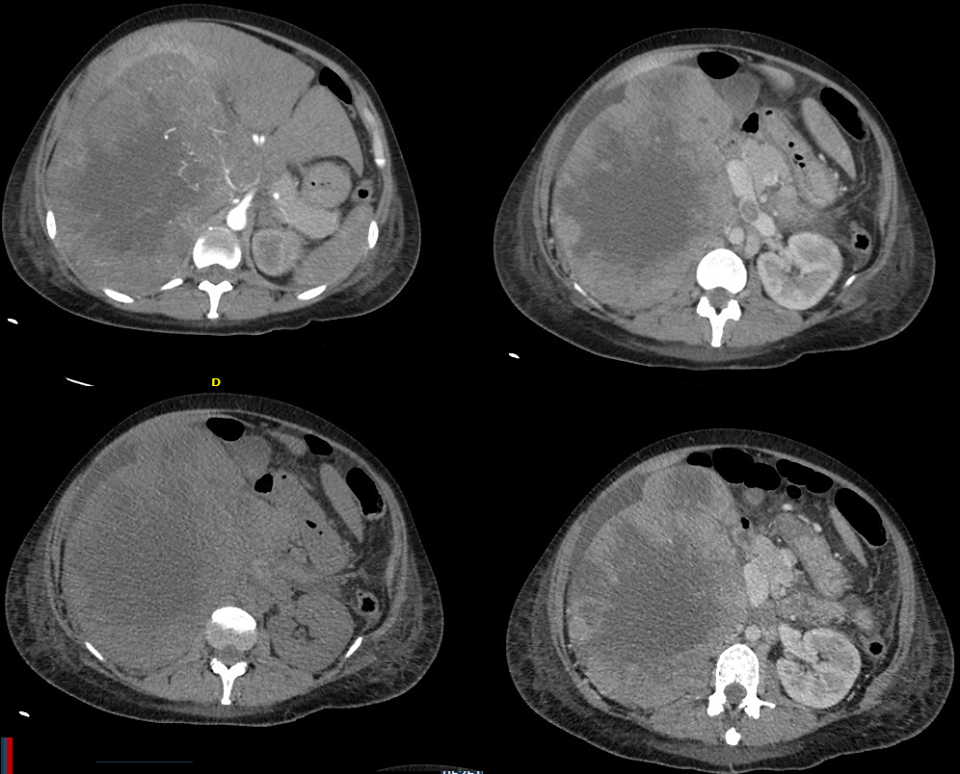

El examen de las muestras de biopsia de la etmoidal posterior izquierda y senos esfenoidales mostraron mucosa nasosinusal con un tejido linfoide denso subyacente en un fondo de la fibrosis. Las células linfoides eran grandes, y la tinción inmunohistoquímica para CD20, un antígeno de células B, fue positivo, lo que confirma el diagnóstico de linfoma difuso de células B grandes (Figura 3A, 3B y 3C).

Figura 3

Biopsia muestras de la Izquierda Posterior etmoides y esfenoides senos

En la tinción con hematoxilina y eosina, las muestras de biopsia del etmoides posterior izquierda y senos esfenoidales revelaron mucosa nasosinusal con un tejido linfoide subyacente infiltrante en un fondo de fibrosis moderada (Panel A). Las células linfoides eran grandes, con núcleos irregulares multilobulados, cromatina vesicular y nucleolos prominentes ocasionales (Grupo B). La tinción inmunohistoquímica para CD20 fue difusamente positiva (Grupo C), lo que confirma el diagnóstico de linfoma difuso de células B. En la tinción inmunohistoquímica adicional, las células tumorales fueron difusamente positiva para CD10 (Panel D) y CD30 (Panel E), y la mayoría de las células tumorales eran de forma variable positiva para el linfoma de células B 2 proteínas (BCL2) (Panel F).

El linfoma difuso de células B representa un grupo de cánceres biológicamente heterogéneos que se pueden dividir morfológica, genética e inmunofenotípicamente y que incluyen ciertas entidades específicas.14 La mayoría de los casos no cumplen los criterios diagnósticos de una de las entidades patológicas específicas y son clasificados como linfoma difuso de células B. Un examen más detallado inmunofenotípico del tumor de esta paciente reveló que las grandes células B fueron positivas para antígenos del centro germinal CD10 y linfoma de células B 6 proteínas (BCL6) y fueron negativos para el post-germinal centro mieloma múltiple marcador oncogén 1 (MUM1, también conocido como factor regulador de interferón 4), los hallazgos que indican que el linfoma es de origen germinal-centro, en lugar de origen nongerminal-centro (Figura 3D) 0,15 mayoría de las células tumorales fueron positivas para la proteína antiapoptótica marcador linfoma de células B (2 BCL2) (Figura 3F), 50% de las células tumorales fueron positivas para el antígeno de proliferación Ki-67, y 10% de las células tumorales fueron positivas para MYC. La ausencia de una alta expresión concurrente de BCL2 y MYC indica que este tumor está en un subgrupo de linfoma difuso de células B que se asocia con un mejor pronóstico, en comparación con el subgrupo de tumores que muestran alta expresión concurrente de MYC y BCL2.16 , 17 Las células tumorales fueron también fuertemente y de forma difusa positivas para CD30, un antígeno de activación (Figura 3E); un ARN en el ensayo de hibridación in situ fue negativo para el virus de Epstein-Barr.